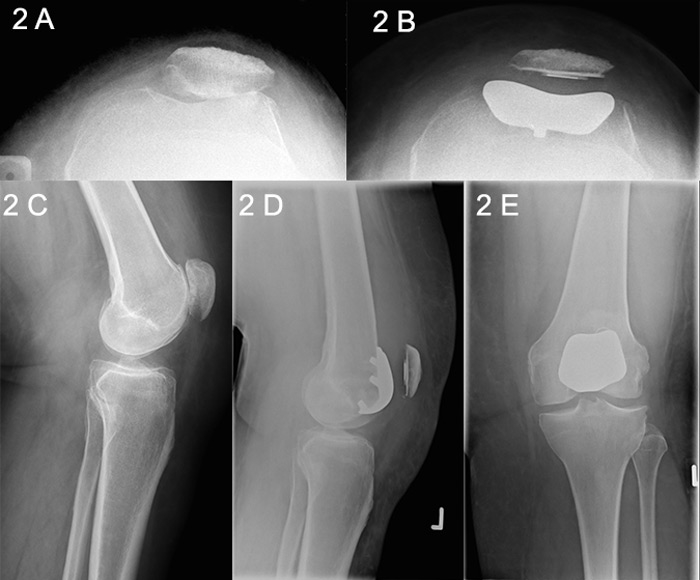

Figure 2

Patellofemoral joint (PFJ) arthritis.

A. Skyline X-Ray showing PFJ osteoarthritis. B. Skyline X-ray after PFJ replacement. C. Lateral X-ray showing PFJ osteoarthritis. D. Postoperative lateral X-ray after PFJ arthroplasty. E. Anteroposterior X-ray after PFJ arthroplasty.

The first patellar prosthesis was described by McKeever in 1955, followed by the first femoral component 24 years later, as described separately by Lubinus and Blazina [19, 20]. Enhanced second-generation prostheses with a broad symmetrical trochlear flange evolved in the 1990s, and the design has been refined and updated continually in the intervening years (fig. 2 A‒E) [21]. The Cochrane-registered Warwick trial was designed to determine whether there is a difference in functional knee scores and quality-of-life outcomes, as well as complication rates, between patellofemoral arthroplasty and TKA in patients with severe PFJ arthritis. Reports of the trial are currently awaited [22].